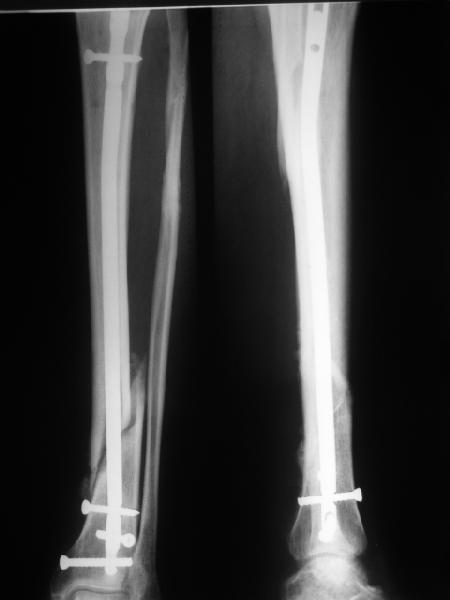

"Ходит с ограниченной нагрузкой на ногу. Направлен из травмпункта по поводу оставшегося смещения отломков. У нас разделилось мнение коллег по вопросу - есть ли необходимость в закрытом интрамедуллярном реостеосинтезе с исправлением оси или только ограничиться динамизацией гвоздя"

Техника введения штифта в дистальные переломы голени отличается от введения в c/3 диафиз. В дистальном отделе штифт надо ввести поглубже и блокировку внизу сделать на все возможные дистальные отверстия. В верхней части короткий штифт создает запас для будущей динамизации.

На снимке сохранен небольшой вальгус, но имеется нормальная аппозиция медиального кортикального слоя и поэтому трудно согласится что здесь имеется неправильно фиксированный перелом. Для идеального сопоставления таких косых переломов надо открывать фокус травмы, но тогда меняется философия фиксации.

Навряд ли рискованные манипуляции в фокусе травмы или ре-остеосинтез улучшит результат кроме рентгенологической картины.

Для предупреждения осложнении можно оставить как есть, потому что всего месяц с момента операции и не видно признаков несостоятельности остеосинтеза.

Отсутствие болей показания к нагрузке и после восстановления движения в суставе через пару-три недели можно сделать динамизацию. За редким исключением, обычно такие “неправильно фиксированные” переломы сростаются в срок.

Все наши сомнения связаны с тем, что этих незначительных погрешностей (небольшой вальгус, неглубоко пробит гвоздь, мало запирающих винтов в

дистальном отломке) не одна, а несколько, и вместе они могут значительно осложнить дальнейшую жизнь пациенту. В нашей практике были подобные случаи, при которых после разрешения полной нагрузки либо начинала увеличиваться деформация, либо происходил перелом гвоздя по ближайшему отверстию. Кроме того, при диафизарных переломах, имея в арсенале надежный фиксатор, нет никакой необходимости вынуждать пациента ограничивать нагрузку на ногу в течении 2-3 месяцев.

Взвесив все <<за>> и <<против>>, мы приняли решение и выполнили реостеостинтез: выбили гвоздь до линии перелома, провели отклоняющую

спицу, забили обратно гвоздь и заблокировали внизу 3-мя винтами, вверху одним. Вся операция заняла меньше часа. Сегодня пациент ушел от нас домой с полной нагрузкой на ногу.